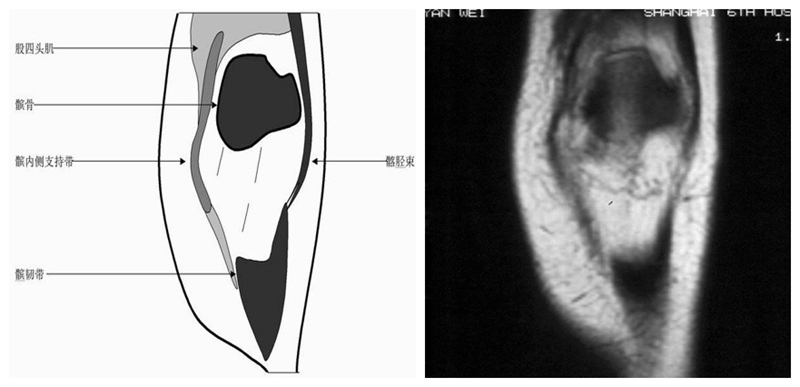

膝关节矢状面正常解剖MRI表现

可整段显像髌韧带、前后交叉、外侧韧副带结构,侧重的股胫软骨中部和半月板前后角,通常是诊断半月板撕裂或变性最为关键的断面。

矢状位解剖第一层

矢状位解剖第二层